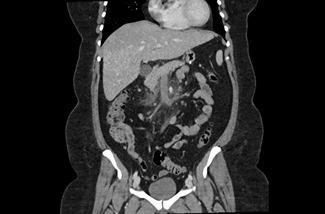

The initial physical examination showed a patient in discomfort but with normal vital signs. The abdominal palpation revealed epigastric tenderness without guarding or without other signs suggestive of acute abdomen. Surgical sites appeared to be well-healed, clean, and dry with no evidence of drainage or dehiscence. The laboratory analyses showed elevated inflammatory parameters (13,500 leukocytes and a C-reactive protein level of 123,20 mg/dL) and normal levels of amylase and lipase. A contrast-enhanced abdominopelvic computed tomography (CT) scan (Figures 1, 2, and 3) showed a dilatation in the mesenteric vessels, particularly the superior mesenteric vein, which had a luminal filling defect near its confluence with the splenic vein. The CT scan also revealed thickening of the adjacent adipose tissue, albeit without signs of intestinal ischemia. The patient was admitted to ward and started on LMWH 100 mg every 12 hours along with reinforced IV hydration. After three days in the hospital, she was discharge home asymptomatic. Anticoagulation therapy was continued with LMWH for one month before transitioning to a non-vitamin K antagonist oral anticoagulant (NOAC), specifically Apixaban 5 mg every 12 hours, and the use of estrogen for birth control was discontinued. At the three-month follow-up, the patient had lost 20 kg and was scheduled to repeat the CT scan and to discontinue anticoagulation therapy approximately six months after the thrombotic event.

Figure 2 CT scan showing thrombosis of superior mesenteric vein – sagital image.